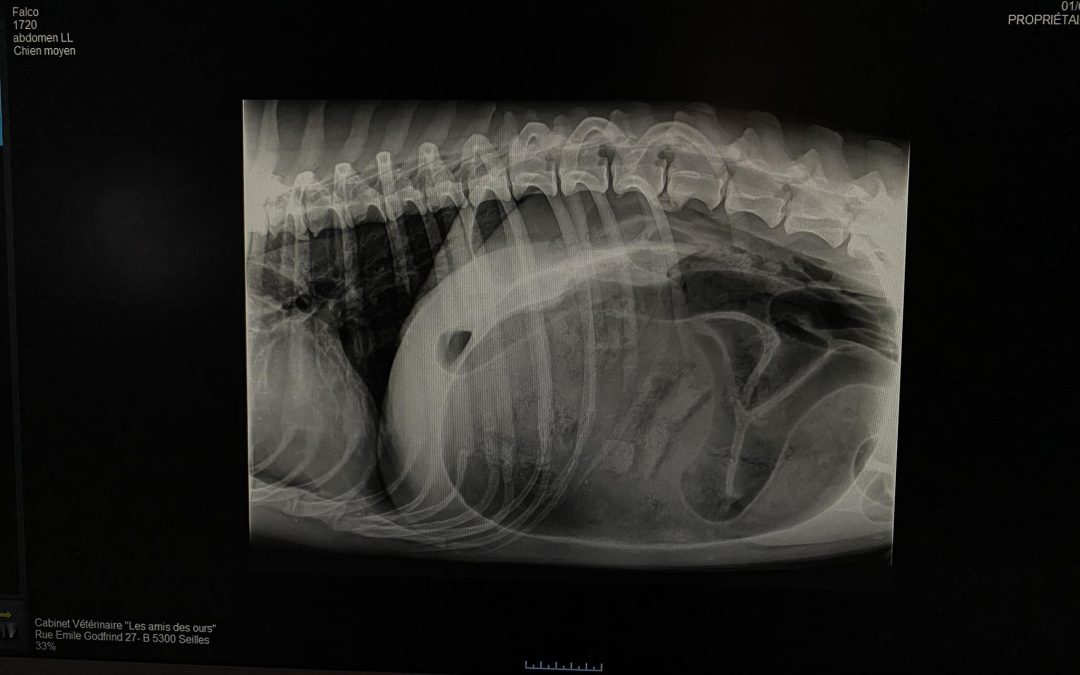

- La chirurgie n’a pas été évidente à cause de la taille de l’estomac. Comme on peut le voir sur la radio, celui-ci prend toute la place. Il faut alors le retourner dans sa position physiologique, s’assurer qu’il n’y ait pas de signe de souffrance des tissus, le vider et le fixer afin d’éviter qu’il ne rebascule.